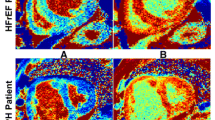

The T1-values of the RV were assessed using cvi42 (Circle Cardiovascular Imaging). As previously described [22], a ROI contour was traced manually on the T1 maps of inferior RV region avoiding the RV insertion point (Fig. 2); attempts were made to draw ROI in RV anterior and RV free-wall regions but this was not feasible. The ROI was carefully drawn within myocardial walls to avoid partial volumes and epicardial fat (Fig. 2). For the LV, the endocardial and epicardial contours were manually traced and was sub-divided into 6 equiangular segments based on a standard AHA segmentation [20]. A mean myocardial T1 value was obtained within each segment.

Representative case inferior wall right ventricular (RV) native T1-mapping in Pulmonary Artery Hypertension (PAH) and healthy control group. Representative case with the region of interest (ROI) contour (white arrow) traced manually on the T1 maps of inferior segment of RV in a PAH and b healthy control groups